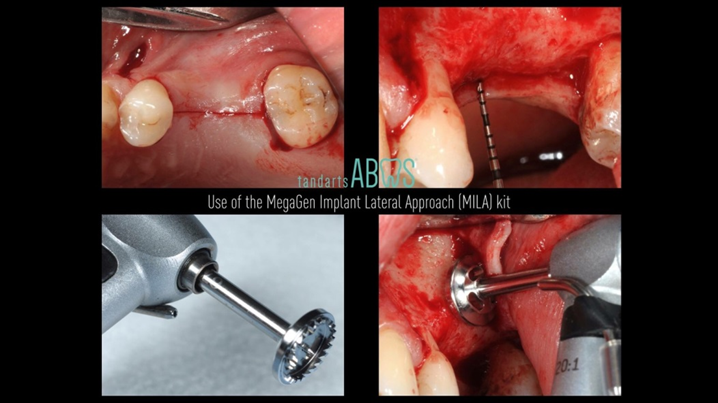

Klinikinis atvejis: Vėlyvoji implantacija: viršutinio žandikaulio ančio dugno elevacija, implanto sriegimas ir kraštinė kaulo regeneracija;

- Dr. Irfan Abas klinikinis atvejis -

Vėlyvoji implantacija, ančio dugno elevacija, ančio dugno elevacija atviru būdu, kraštinė kaulo regeneracija, Dr. Irfan Abas, AnyRidge, MiLA chirurginis rinkinys, kaulo regeneracija;

AnyRidge implantų sistema, MILA chirurginis rinkinys;